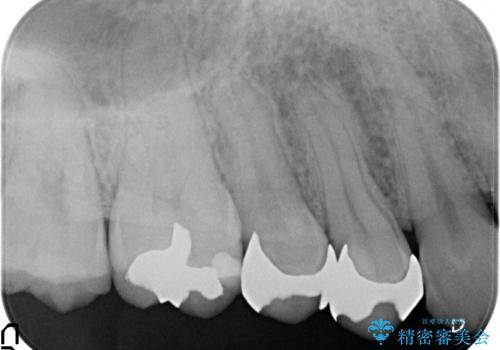

- 右上の銀歯を白くしたいといらっしゃった方の症例です。

右上4、5番目の歯はオールセラミッククラウンによる補綴、6番目の歯はセラミックインレーによる修復を行いました。